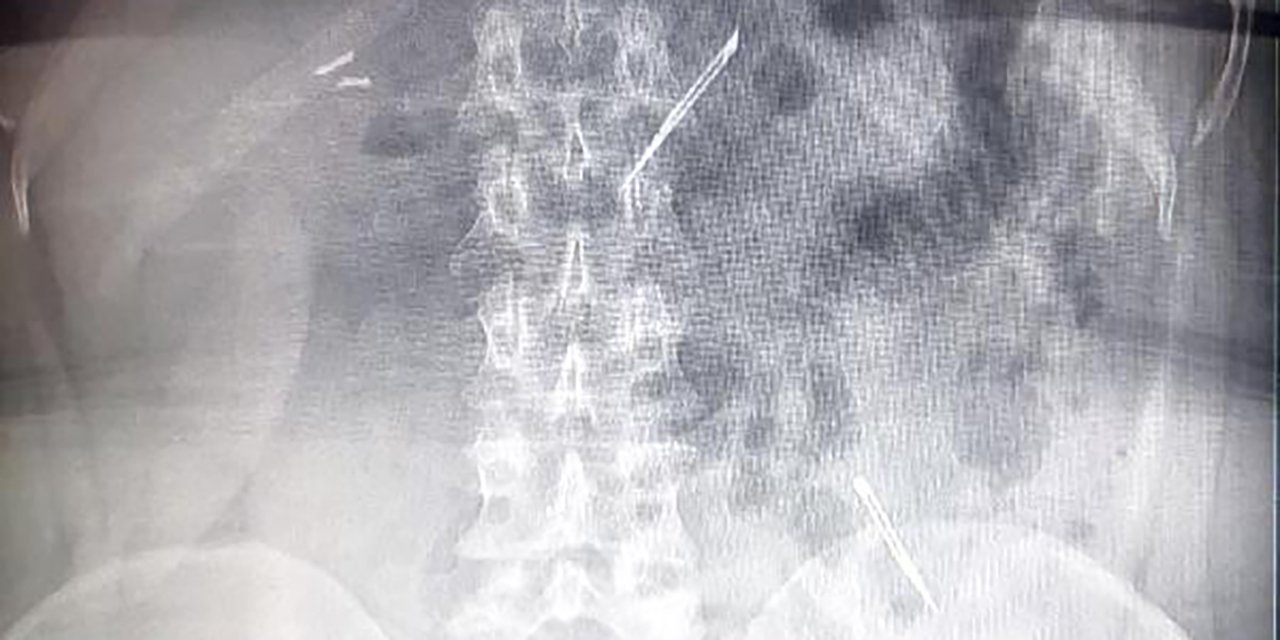

Ağrıları artınca ameliyata alındı, çıkanlar doktorları da şaşırttı